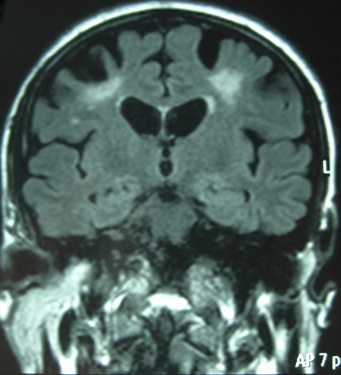

Un homme, âgé de 63 ans, marié, ancien infirmier, aux antécédents d’HTA résistante, d’AIT (trouble phasique) sur passage en ACFA traitée par anticoagulants 4 ans plus tôt, d’épilepsie généralisée depuis un an traitée par Carbamazépine, de cécité de l’œil droit suite à un décollement de rétine et d’hypoacousie bilatérale, se plaignait d’un trouble phasique anciens et plus récemment de pseudovertiges.